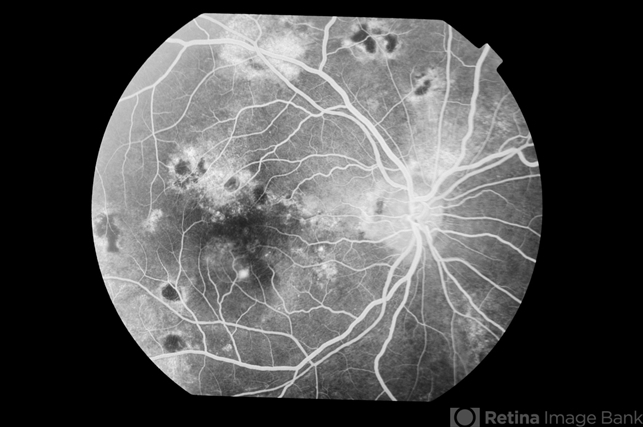

- Multiple leak recurrent CSCR

- central serous chorioretinopathy (CSCR), retinal pigment epithelium (RPE) defect, bilateral recurrent CSCR

- Right eye fluorescein angiogram of a 37-year-old lady with bilateral recurrent CSCR; multiple areas of RPE transmission defects and a single active RPE leak inferotemporal to foveal centre.